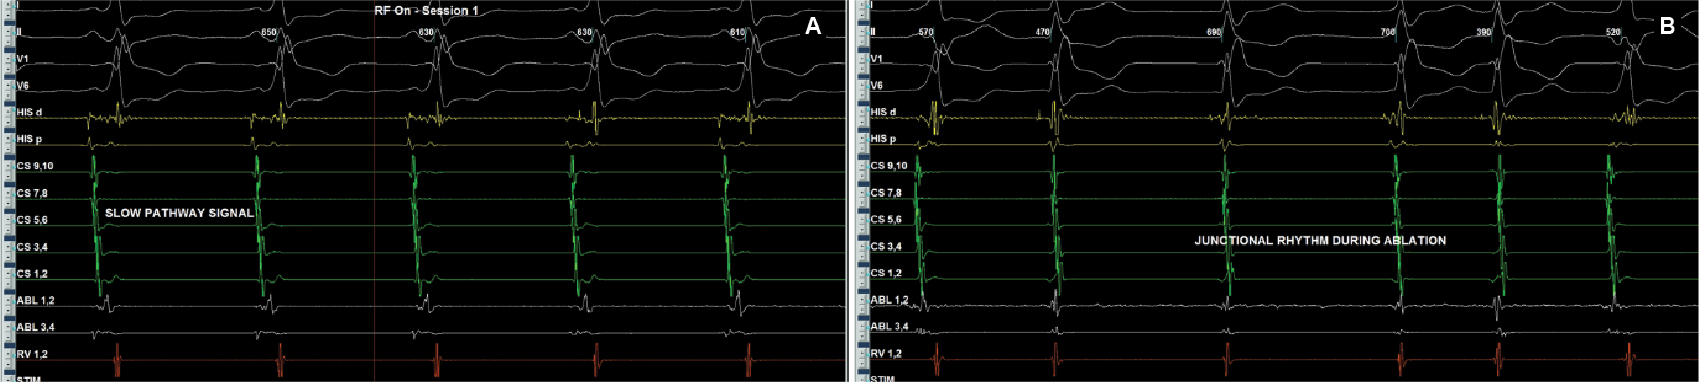

After written informed consent, patient was taken for electrophysiological study. Two quadripolar diagnostic catheters were advanced under fluoroscopy to His bundle region and right ventricular apex. One decapolar catheter was advanced into the coronary sinus. During the electrophysiological study at baseline, atrial-His bundle (AH) and His-ventricular (HV) intervals were 85 ms and 3 ms in sinus rhythm, respectively. There were no atrioventricular (AV) conduction abnormalities. A narrow complex tachycardia (tachycardia cycle length [TCL] = 400 ms) was easily induced during catheter placement with following features: initiation of the tachycardia with a critical AH interval, fixed 1:1 ventriculoatrial (VA) conduction, concentric retrograde activation with VA interval of 37 ms, a post-pacing interval (PPI, 576 ms)–TCL (406 ms) >115 (170 ms) and ventricular overdrive pacing resulted in a VAHV response. His synchronized and early premature ventricular contraction (PVC) did not reset the tachycardia. His synchronized premature atrial contraction (PAC) also failed to reset the tachycardia. The tachycardia was reproducible and consistent (Fig. 2). After confirming the diagnosis of typical AV nodal re-entrant tachycardia (AVNRT) a decision was taken for slow pathway ablation. Using a steerable ablation catheter, with the help of intracardiac electrograms (EGMs) and using fluoroscopy, the region of the slow pathway was identified. Radiofrequency applications were made in the region of the slow pathway while constantly monitoring temperature, impedance, ECG and intracardiac EGMs, monitoring for fast junctional conduction and radiofrequency energy was halted if there was evidence of VA block. Radiofrequency ablation resulted in a junctional rhythm with intact AV conduction, which is a typical response. The AV nodal slow pathway was successfully modified (Fig. 3).

Figure 3. Slow pathway signals (A) at rightward inferior extension showed fused signals because of underlying pathway. Junctional rhythm (B) in response of radiofrequency energy.